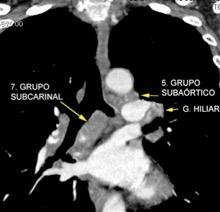

Triada de Garland

Ganglios paratraqueales derechos e hiliares bilaterales

95% de pacientes tienen ganglios hiliares bilaterales aislados o con afectación mediastínica (espec. paratraqueal derecho).

Criado E et al. Pulmonary sarcoidosis: typical and atypical manifestations at high-resolution CT with pathologic correlation. Radiographics. 2010

Depresión ligera…….55% profunda. 35%

FRECUENTES Ganglios. (más frecuente)

Webb R. 2005 Aneurisma aórtico Disección aórtica con aneurisma Masa mediastínica (incl. Ca. de pulmón)

Boiselle PM et-al. Imaging of mediastinal lymph nodes: CT, MR, and FDG PET. Radiographics. 1998

Ganglios frecuentes

Sarcoidosis

Ca. de pulmón

Metástasis

Esófago Mama

Tiroides Mesotelioma

T. Tímico

Kligerman S Abbott G.A Radiologic Review of the New TNM Classification for Lung Cancer. AJR.2010